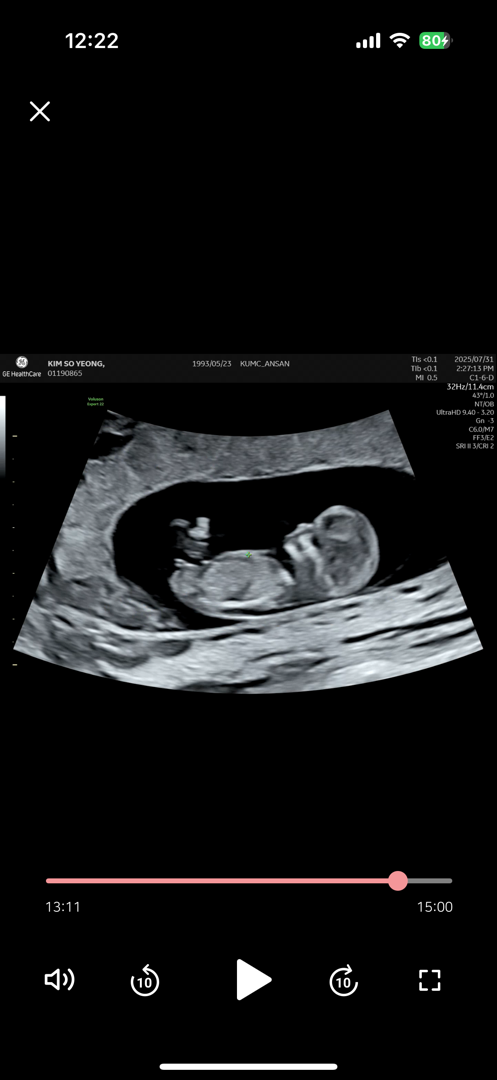

11주 아들일까요 딸일까요~~?!!

아들인것 같기도하고~~~딸인것 같기도하고~~ 유튜브 각도법은 다 찾아본거같아요🤭